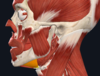

מה מסומן בחץ מספר 1?

Orbicularis Oculi m

מה מסומן בחץ מספר 2?

Zygomaticus Minor m

מה מסומן בחץ מספר 3?

Masseter m

מה מסומן בחץ מספר 4?

Parotid duct and gland

מה מסומן בחץ מספר 5?

Buccinator m

מה מסומן בחץ מספר 6?

Zygomaticus major m

מה מסומן בחץ מספר 7?

Orbicularis Oris m